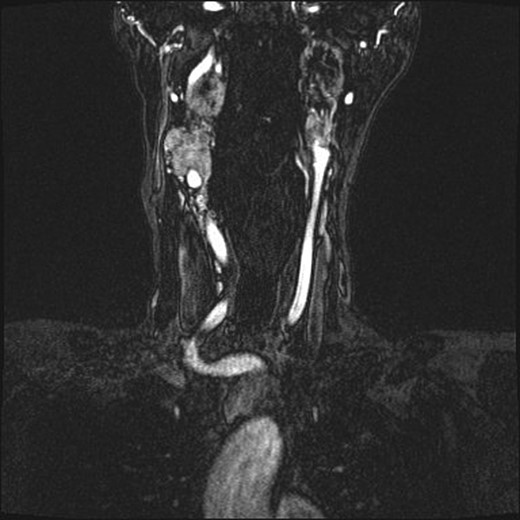

Repeat magnetic resonance imaging (Figs. 3 and 4) showed increased left-sided carotid PGL, significant extension into the jugular foramen and skull base, and associated high-grade tumor compromise of the left internal carotid artery; no radiologic evidence suggested intracranial ischemic sequelae. Computed tomographic (CT) imaging showed infiltration of the left petrous and clivus regions of the skull (Fig. 5). Findings were compatible with progression of the previously known tumor.

Magnetic resonance angiogram, coronal plane, shows tumor compromise of the left internal carotid artery.